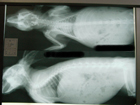

手術をした所。

あえて見にくく小さくアップ^^;

今回の手術を行う時に、どうせ全身麻酔をするならと思って

レントゲン撮影と血液検査をお願いしてありました。

レントゲンを見て先生は・・・

「太ってるんじゃね?」

だって・・・・・・〓■●ポテッ

レントゲン、嘘つかない!です。・・・〓■●ポテッ

レントゲン写真、なんか鳥みたいですよね(笑)

レントゲンは恐竜みたいですよね^^;

レントゲン!!とさかが映ってますわねん^m^

うちの実家のオカメインコにやや似なんじゃね?

レントゲン写真って、なんか不思議な生物に見えるよね~(^^;